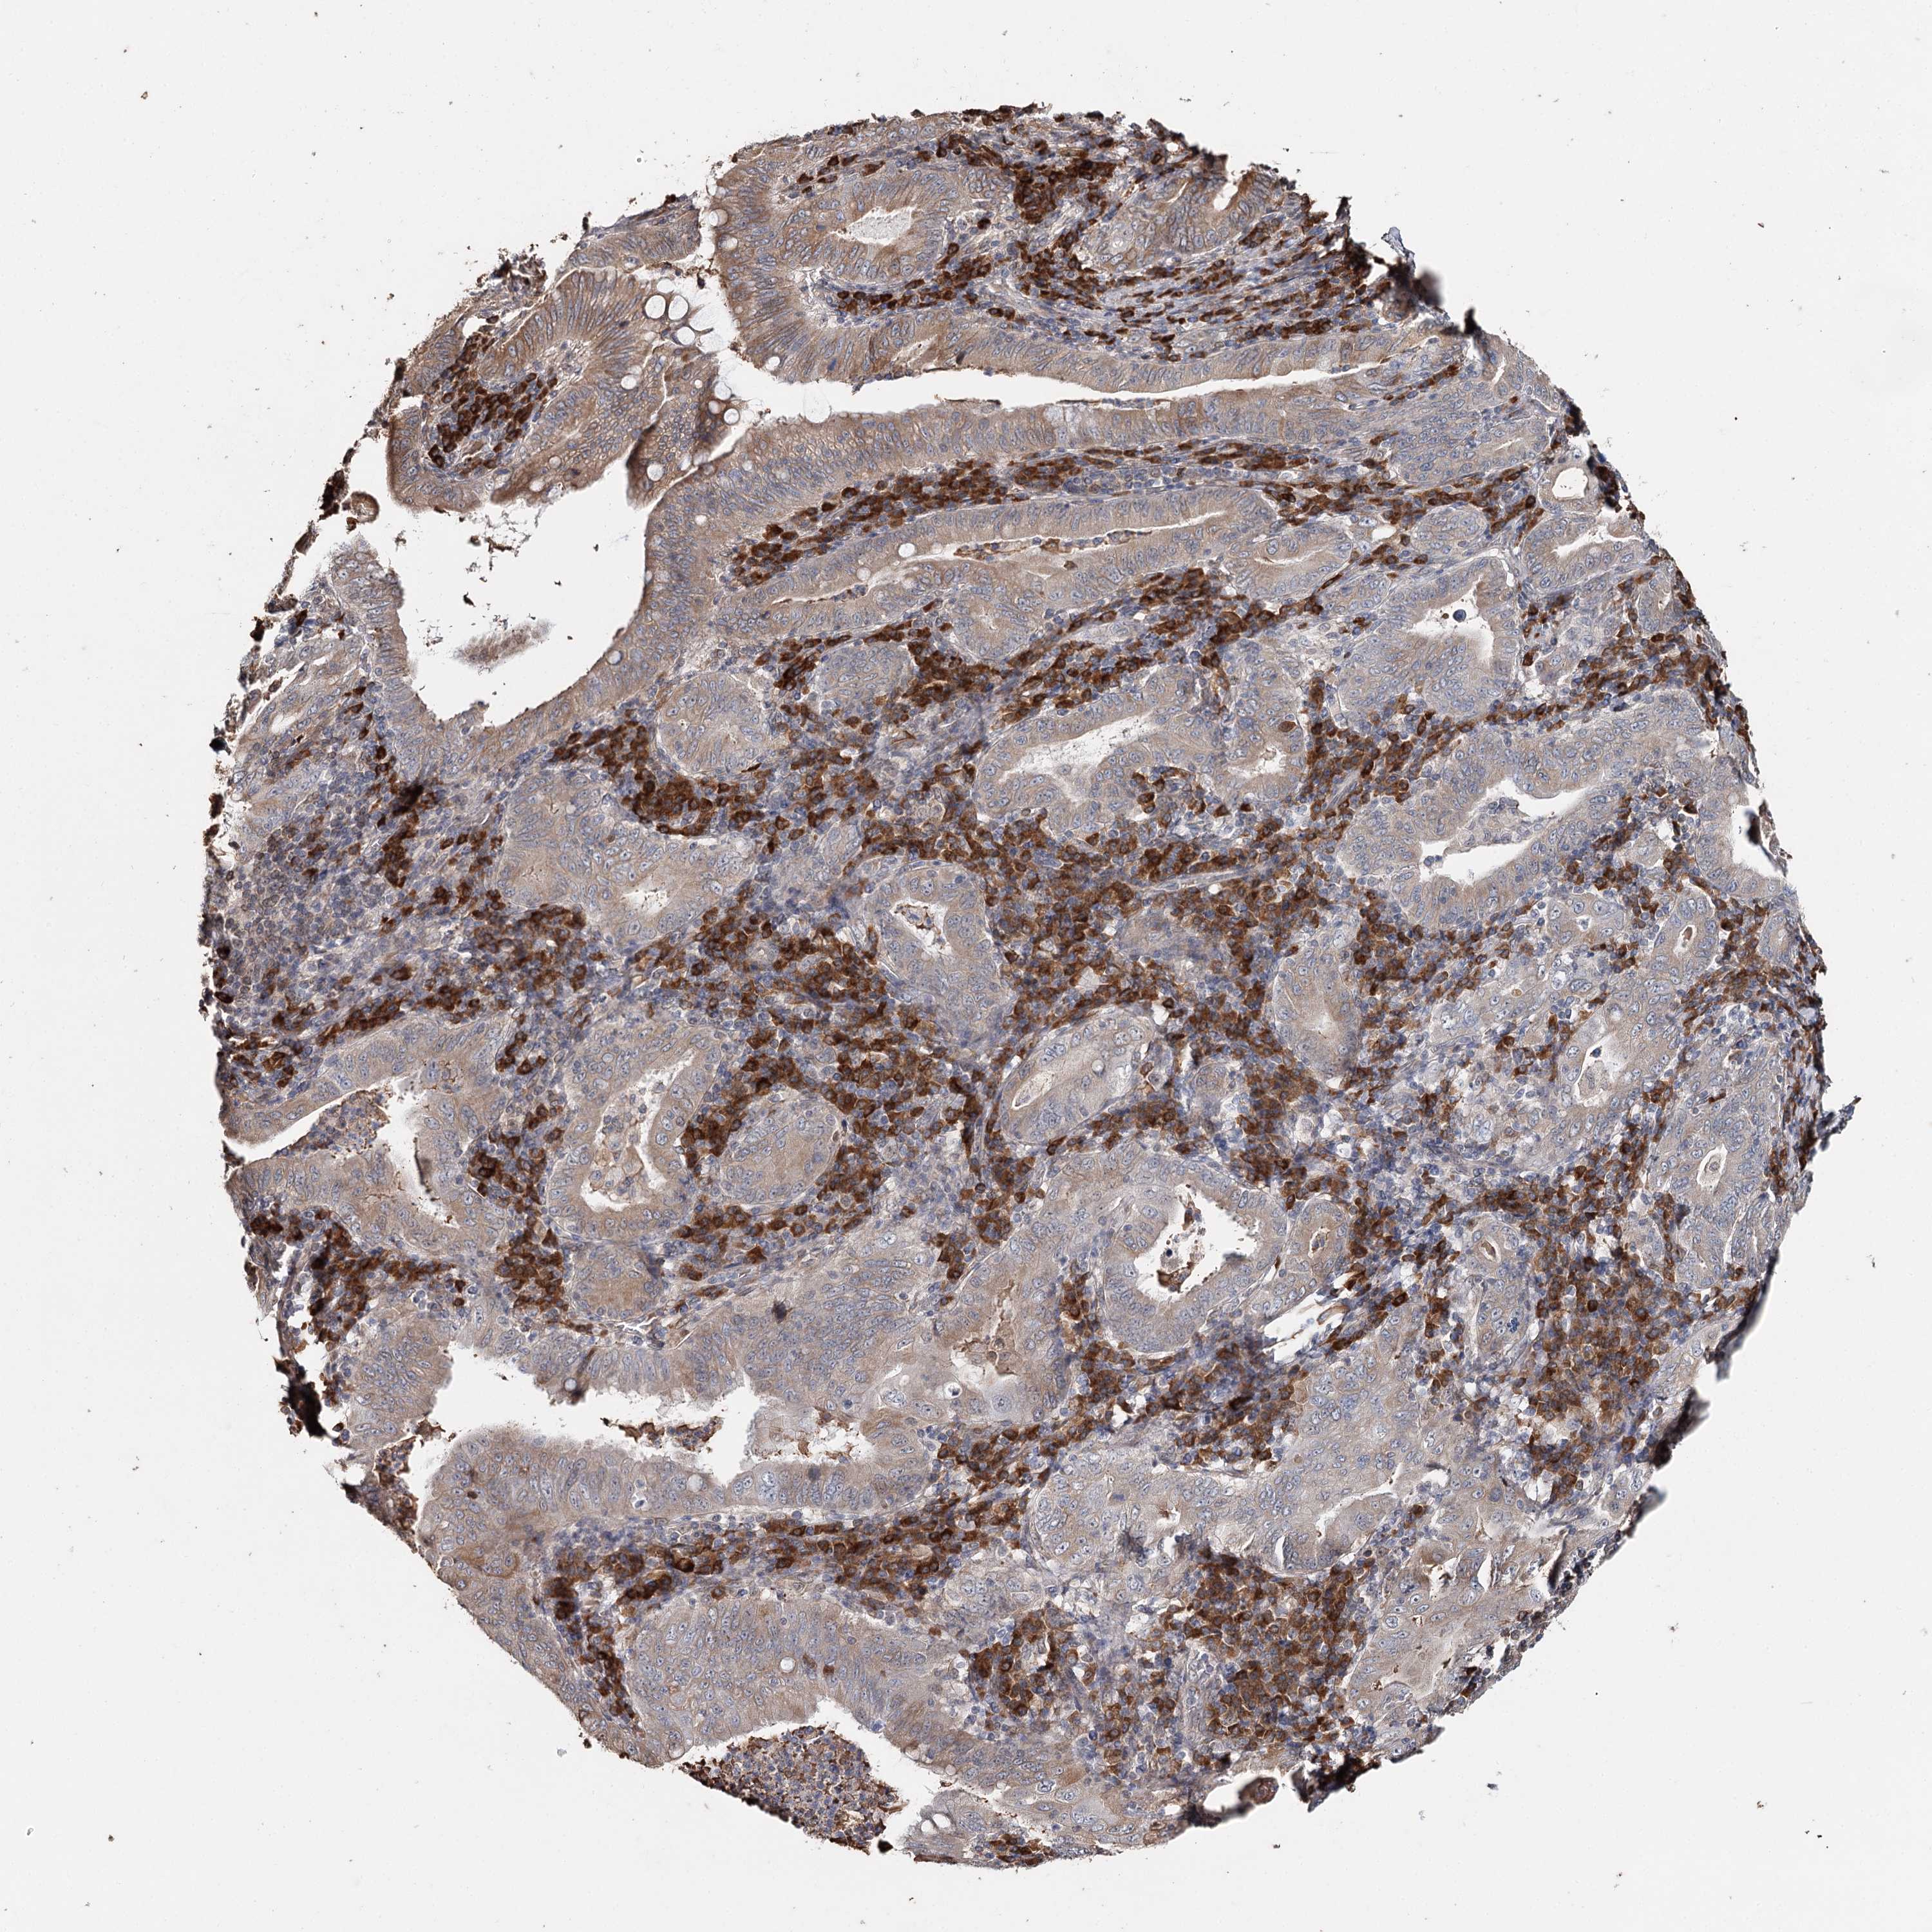

STOMACH CANCER - Protein expressioni

A mouse-over function shows sample information and annotation data. Click on an image to view it in a full screen mode. Samples can be filtered based on level of antibody staining by selecting one or several of the following categories: high, medium, low and not detected. The assay and annotation is described here.

Note that samples used for immunohistochemistry by the Human Protein Atlas do not correspond to samples in the TCGA dataset.

Antibody stainingi

Antibody staining in the annotated cell types in the current human tissue is reported as not detected, low, medium, or high, based on conventional immunohistochemistry profiling in selected tissues. This score is based on the combination of the staining intensity and fraction of stained cells.

Each image is clickable and will lead to virtual microscopy that enables deeper exploration of all samples and also displays staining intensity scores, fraction scores and subcellular localization as well as patient and tissue information for each sample.

Antibody HPA005480

Antibody HPA024300

Antibody CAB037030

Staining

High

Medium

Low

Not detected

Intensity

Strong

Moderate

Weak

Negative

Quantity

>75%

75%-25%

<25%

None

Location

Nuclear

Cytoplasmic/membranous

Cytoplasmic/membranous,nuclear

Adenocarcinoma, NOS

Adenocarcinoma, High grade